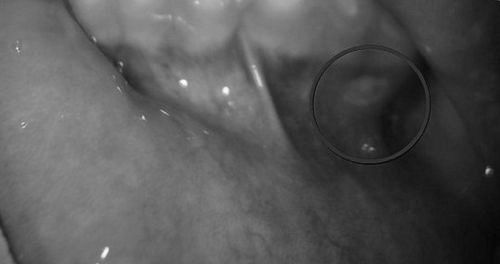

У міру розвитку патології в порожнині рота утворюються афти - невеликі окремо розташовані або згруповані виразки діаметром до 5 мм. Краї виразок виділяються червонуватим відтінком з сірим нальотом. Зовнішні ознаки афтозного стоматиту показані на фото нижче.

Афти - це ділянки слизової з порушеною цілісністю, які чітко відмежовуються від здорових тканин. Форма виразок - овальна або кругла.